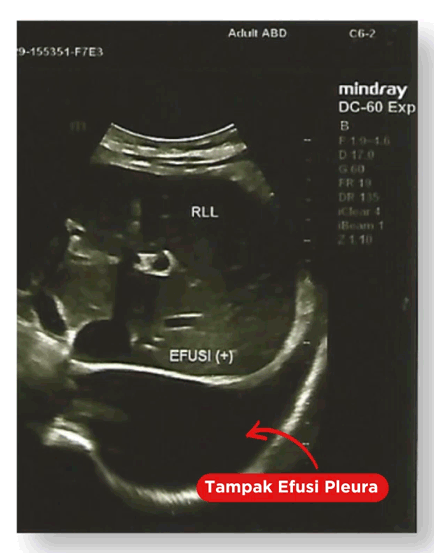

Yuk liat kondisi paru-parunya melalui pemeriksaan USG dibawah ini

Tanda panah menunjukkan adanya cairan yang terdapat di kantung pleura (selaput paru)

Ini hasil pemeriksaan USG pleura / paru. Tidak didapati gambaran hipoechoic sebagai tanda tidak adanya cairan dalam kantung pleura.